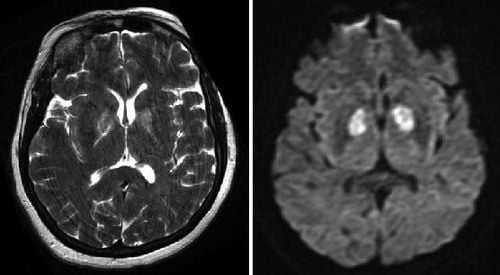

Nhu mô não dưới vỏ nhân bèo 2 bên rải rác có ổ tăng tín hiệu là gì?

Em có đi khám và chụp cộng hưởng từ. Bác sĩ cho em hỏi nhu mô não dưới vỏ nhân bèo 2 bên rải rác có ổ tăng tín hiệu là gì? Em cảm ơn bác sĩ.